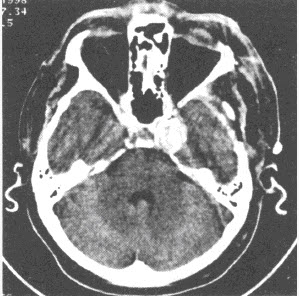

6、单项选择题

患者,男,45岁,头痛半年,CT检查如下图。

A.脑膜瘤

B.垂体瘤

C.动脉瘤

D.星形细胞瘤

E.AVM

F.以上都不是

21、单项选择题

C.胶质瘤

D.神经源性肿瘤

E.转移瘤

22、单项选择题

A.MRI

B.MRA

C.增强扫描

D.DSA

E.手术切开